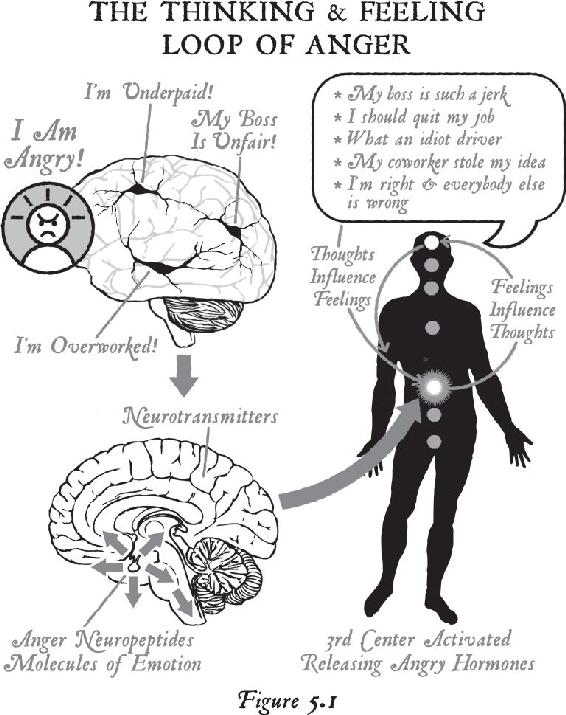

Because of our large brains, human beings are capable of thinking about their problems, reliving past events, or even forecasting future worst-case situations and thus turning on the cascade of stress chemicals by thought alone. We can knock our brains and bodies out of normal physiology just by thinking about an all-too-familiar past or trying to control an unpredictable future.

Every day, Anna relived that event over and over in her mind. What she didn’t realize was that her body did not know the difference between the original event that created the stress response and the memory of the event, which created the same emotions as the real-life experience all over again. Anna was producing the same chemistry in her brain and body as if the event were actually happening again and again. Subsequently, her brain was continuously wiring the event into her memory bank, and her body was emotionally experiencing the same chemicals from the past at least a hundred times each day. By repeatedly recalling the experience, she was unintentionally anchoring her brain and body to the past.

Emotions are the chemical consequences (or feedback) of past experiences. As our senses record incoming information from the environment, clusters of neurons organize into networks. When they freeze into a pattern, the brain makes a chemical that is then sent throughout the body. That chemical is called an emotion. We remember events better when we can remember how they feel. The stronger the emotional quotient from any event—either good or bad—the stronger the change in our internal chemistry. When we notice a significant change inside of us, the brain pays attention to whoever or whatever is causing the change outside of us—and it takes a snapshot of the outer experience. That’s called a memory.

Therefore, the memory of an event can become branded neurologically in the brain, and that scene becomes frozen in time in our gray matter, just as it did for Anna. The combination of various people or objects at a particular time and place from that stressful experience is etched in our neural architecture as a holographic image. That’s how we create a long-term memory. Therefore, the experience becomes imprinted in the neural circuitry, and the emotion is stored in the body—and that’s how our past becomes our biology. In other words, when we experience a traumatic event, we tend to think neurologically within the circuitry of that experience and we tend to feel chemically within the boundaries of the emotions from the event, so our entire state of being—how we think and how we feel—becomes biologically stuck in the past.

As you can imagine, Anna was feeling a rush of negative emotions: tremendous sadness, pain, victimization, grief, guilt, shame, despair, anger, hatred, frustration, resentment, shock, fear, anxiety, worry, overwhelm, anguish, hopelessness, powerlessness, isolation, loneliness, disbelief, and betrayal. And none of those emotions dissipated quickly. As Anna analyzed her life within the emotions of the past, she kept suffering more and more. Because she couldn’t think greater than how she constantly felt, and since emotions are a record of the past, she was thinking in the past—and every day she felt worse. As a psychotherapist, she could rationally and intellectually understand what was happening to her, but all her insights couldn’t get beyond her suffering.

People in her life started treating her as the person who had lost her husband, and that became her new identity. She associated her memories and feelings with the reason she was in her present state. When anyone asked her why she felt so bad, she told the story of the suicide—each time reliving the pain, anguish, and suffering over again. All along, Anna kept firing the same circuits in her brain and reproducing the same emotions, conditioning her brain and body further into the past. Every day, she was thinking, acting, and feeling as if the past were still alive. And since how we think, how we act, and how we feel is our personality, Anna’s personality was completely created by the past. From a biological standpoint, in repeatedly telling the narrative of her husband’s suicide, Anna literally couldn’t get beyond what had happened.

It’s amazing how this can happen to so many people. Because of a shock or trauma in their lives, they never get beyond those corresponding emotions, and their health and their lives break down. If an addiction is something that you think you can’t stop, then objectively it looks as though people like Anna become addicted to the very emotions of stress that are making them sick. The rush of adrenaline and the rest of the stress hormones arouses their brain and body, providing a rush of energy.1 In time, they become addicted to the rush of that chemistry—and then they use the people and conditions in their lives to reaffirm their addiction to the emotion, just to keep feeling that heightened state. Anna was using her stressful conditions to re-create that rush of energy, and without realizing it, she became emotionally addicted to a life she hated. Science tells us that such chronic, long-term stress pushes the genetic buttons that create disease. So if Anna was turning the stress response on by thinking about her problems and her past, her thoughts were making her sick. And since stress hormones are so powerful, she had become addicted to her own thoughts that were making her feel so bad.